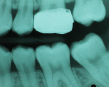

A 9-year-old boy had a partially erupted mandibular first molar with much hypocalcification of the occlusal surface and a large caries lesion involving the occlusal and buccal surfaces (Figure 1). The patient complained of continuing sensitivity to cold stimulus and air inspiration. Because the tooth was only partially erupted, consideration for stainless steel crown full coverage had to be delayed. As an interim repair, it was decided to debride the carious tooth substance and place a light-hardened calcium silicate/mineral trioxide aggregate (MTA) liner, followed by a bonded restoration. After inferior alveolar block anesthetic injection and cotton roll isolation, cavity outline form was cut using a high-speed, water-cooled, medium-grit cylindrical diamond bur (Figure 2). Insufficient eruption precluded use of a rubber dam. A large, round bur at slow speed was used to debride the carious enamel and dentin. The prepared surfaces were swabbed for two 60-second applications of a 5% glutaraldehyde/HEMA solution for desensitization and disinfection of the preparation.6,7 Cavity liner was then injected and spread over the deepest sections of the cavity floor and hardened with the visible light beam (Figure 3). After a self-etching bonding agent was applied over the remaining enamel surfaces, without the need for any type of matrix, an RMGI bioactive ionic resin-based composite was injected, in one portion, into the preparation and spread over the four cusps using a ball burnisher. This restorative complex was then photo-polymerized using two 20-second exposures of the visible light beam (1,200 mW/cm2). The restoration was trimmed and finished with large, round diamond burs at slow speed, and occlusion was evaluated with articulating paper and adjusted.

The repaired molar is shown immediately after treatment (Figure 4) and at 13 months (Figure 5). It was hoped that the restoration of the molar would last long enough that stainless steel crown full coverage would not be needed before precision cast crown placement late in the teen or adult years. However, stainless steel crown coverage could be considered, as needed, pending more eruption of the tooth.

Images of the repaired molar immediately after restoration

Figure 4

13 months postoperatively

Figure 5